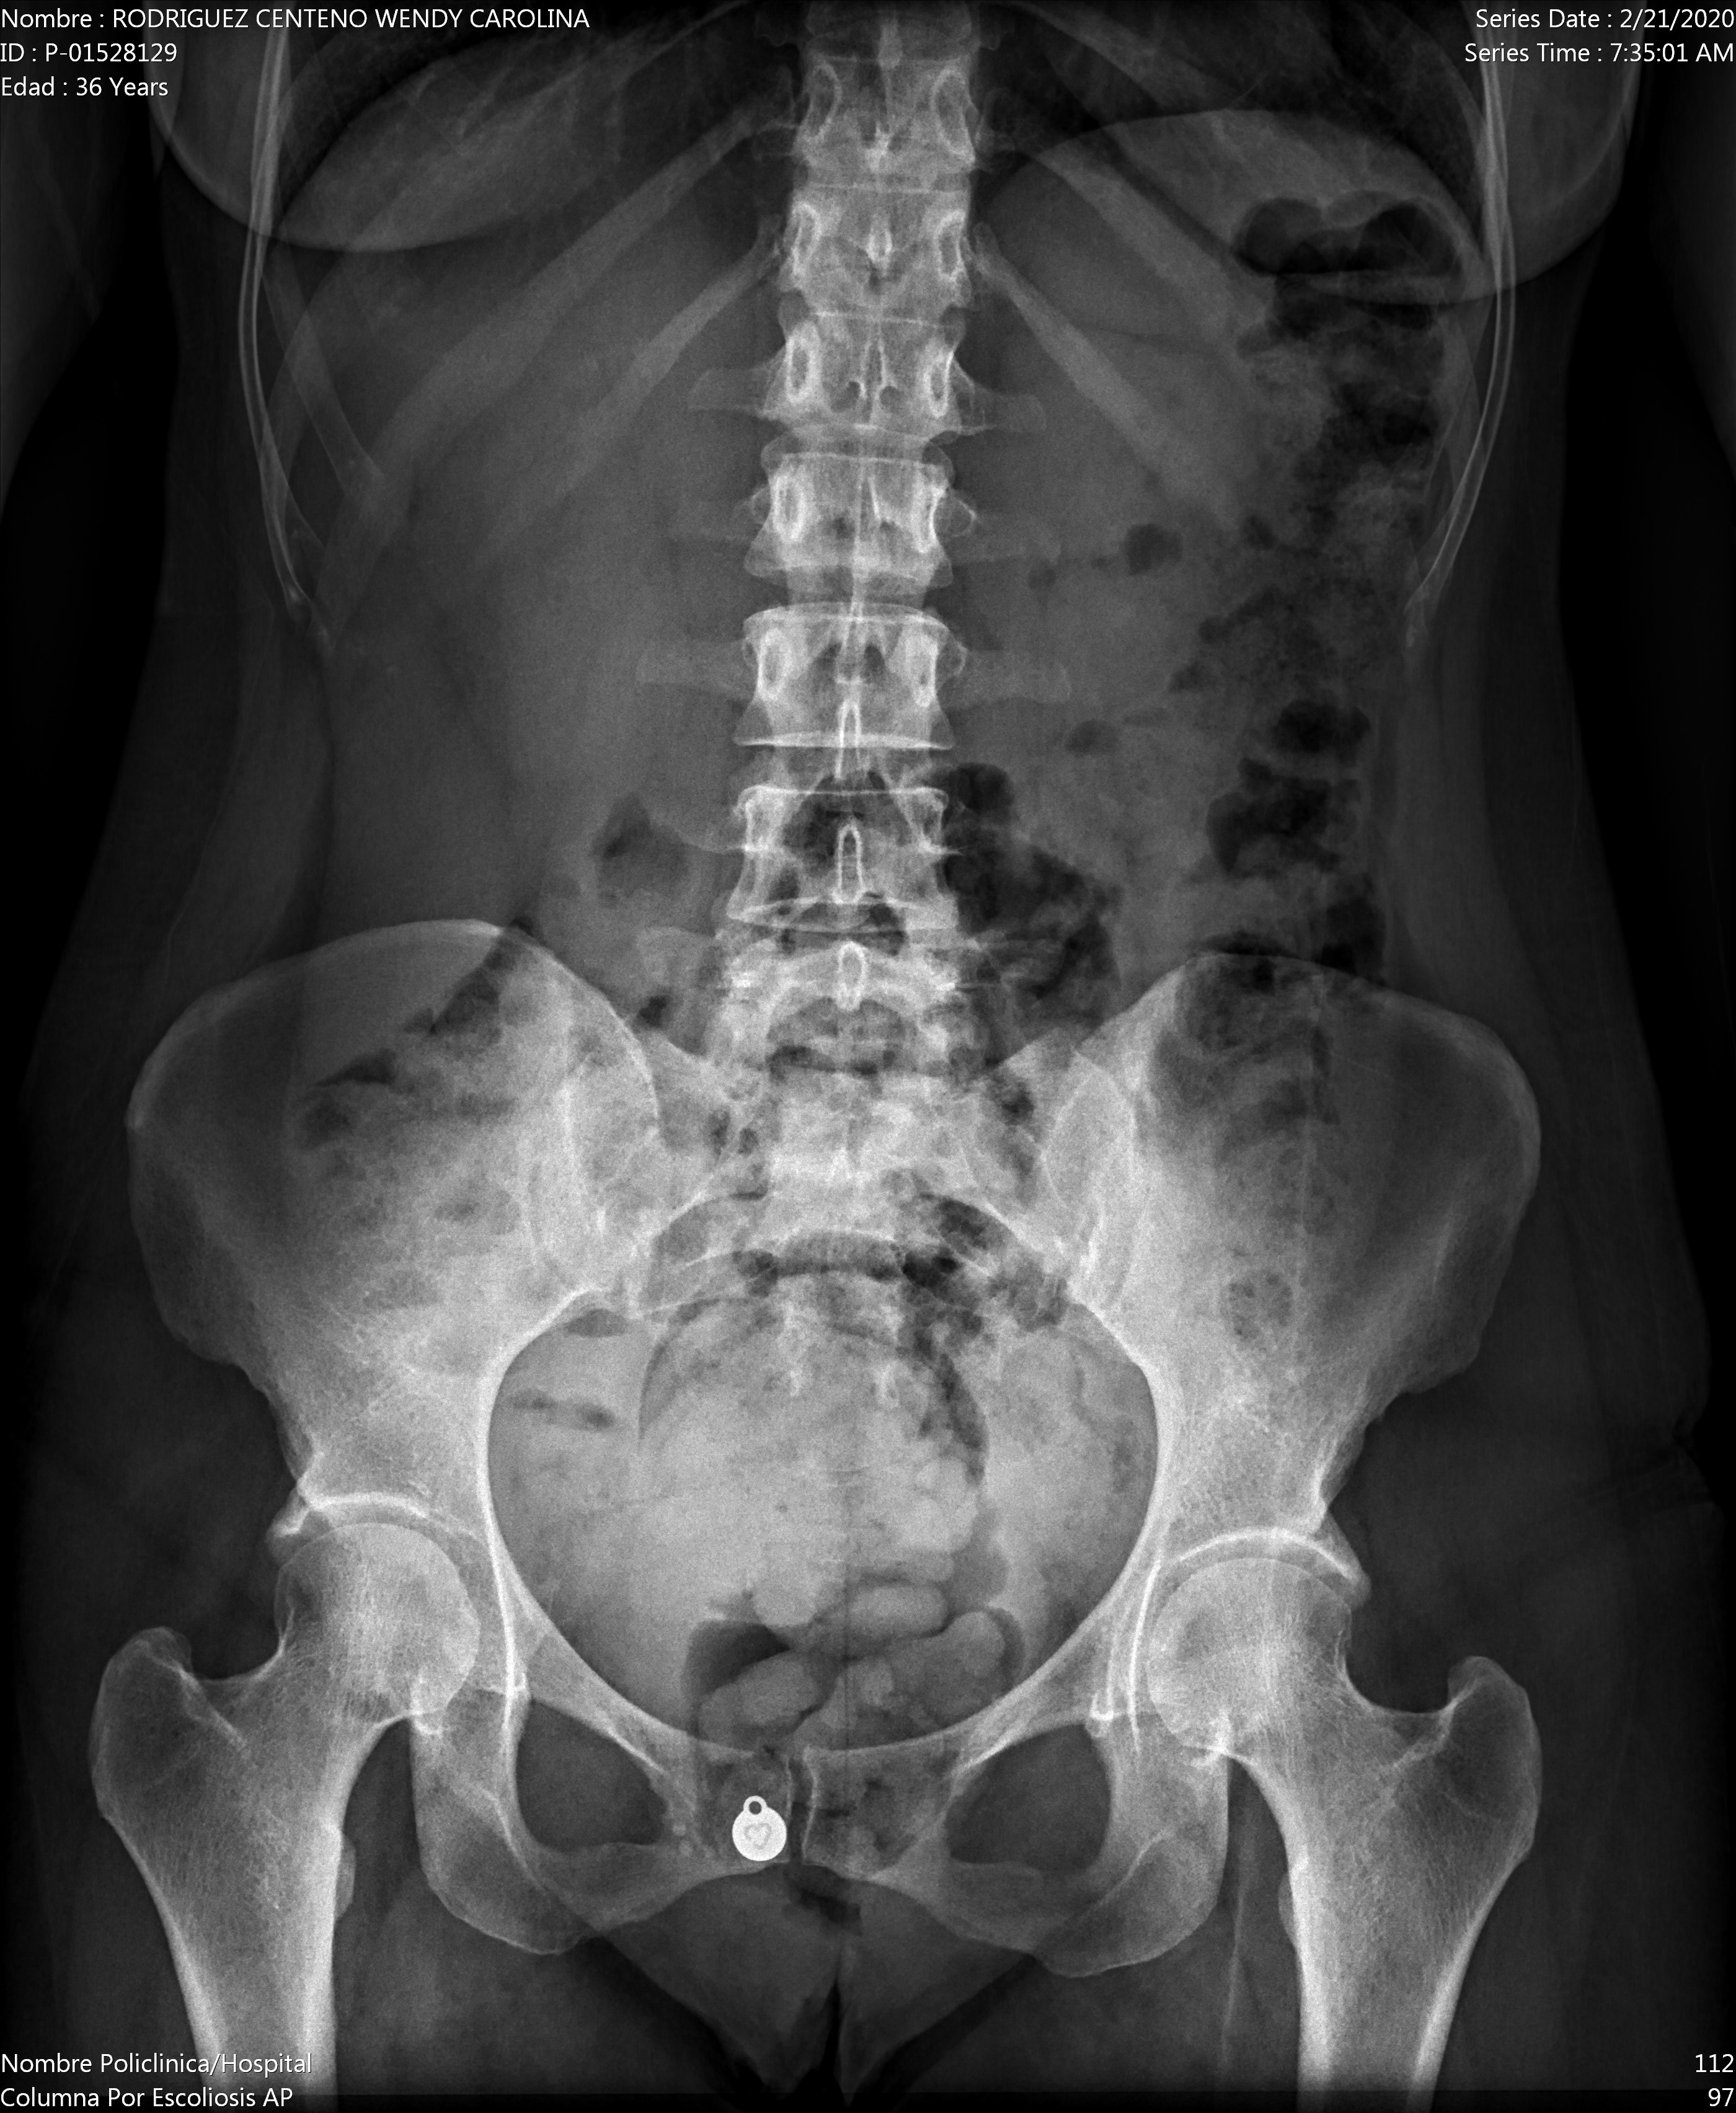

Ho un forte dolore al bacino. Il dolore è più acuto quando devo alzarmi da una sedia e non posso camminare se non lentamente per il forte dolore.

Allego i raggi x appena fatti.

Buongiorno signora. Alle rx non si vede nulla di particolare. Dovrebbe sentire uno specialista quando questa crisi sanitaria sarà risolta. Cordiali saluti